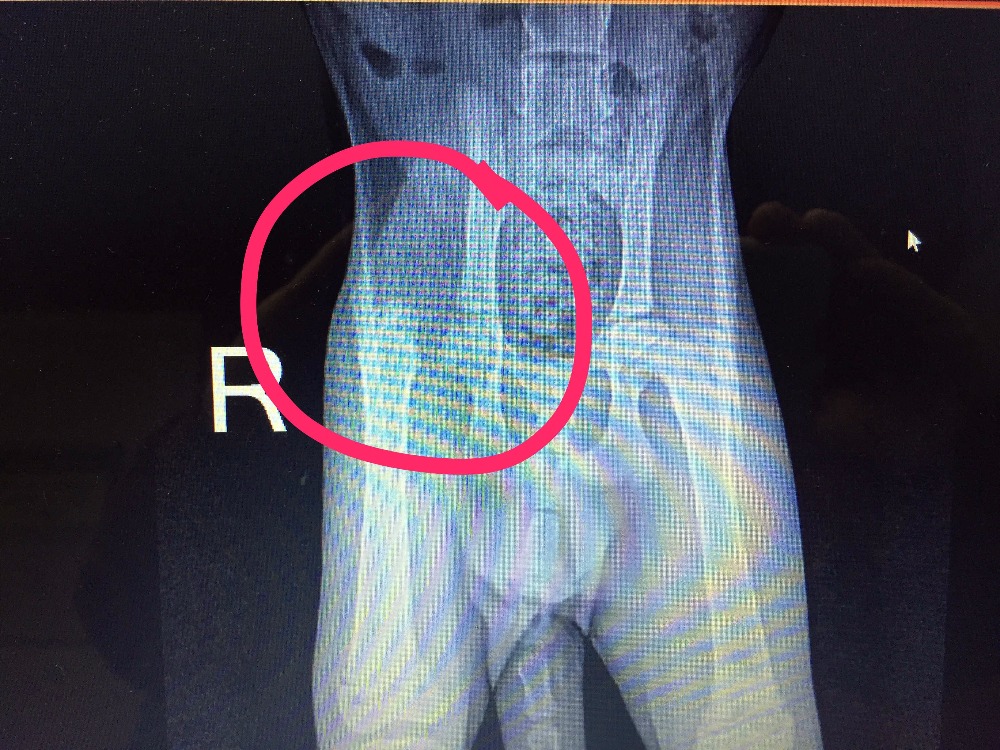

We located another vet that could see her the next day, and we took her in. While she passed all of her major health checks, the x-ray proved that her right hip was not dislocated - instead, her right femur was broken right at the hip joint. The vet indicated that this type of injury is usually associated with severe trauma like a car accident or abuse.